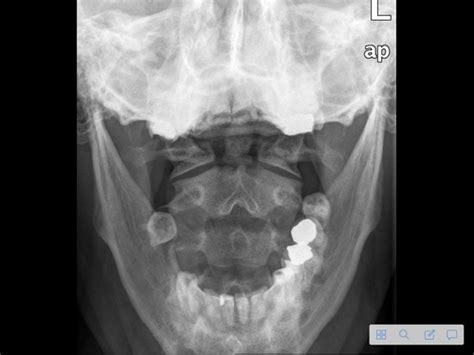

Neurological scenarios could involve stroke, seizures, and headaches. Practice your neurological examination skills, including assessing cranial nerves, motor strength, and sensory function. Know the Glasgow Coma Scale and be familiar with common neurological medications. Musculoskeletal cases often involve joint pain, back pain, and fractures. You should be able to perform a musculoskeletal examination, assess range of motion, and interpret X-rays. Be prepared to discuss management options, including pain relief and rehabilitation. Endocrine scenarios might include diabetes, thyroid disorders, and adrenal insufficiency. You’ll need to demonstrate your ability to assess blood glucose levels, interpret thyroid function tests, and manage hormonal imbalances. Practice your patient education skills, especially regarding insulin administration and dietary modifications.